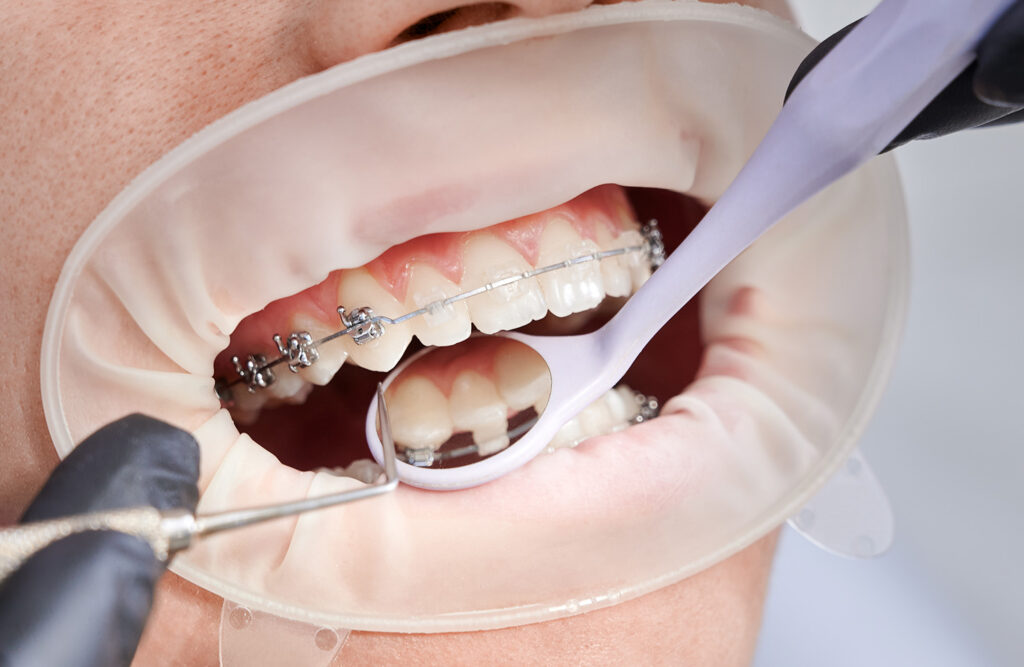

ゴムメタルワイヤー矯正

柔らかく、しなやかでありながら高強度という性質がある「ゴムメタル」という金属のワイヤーを使用する矯正方法です。

歯を3次元で動かしやすいため、ほとんどの症例で小臼歯の抜歯せずに矯正治療が可能となっています。